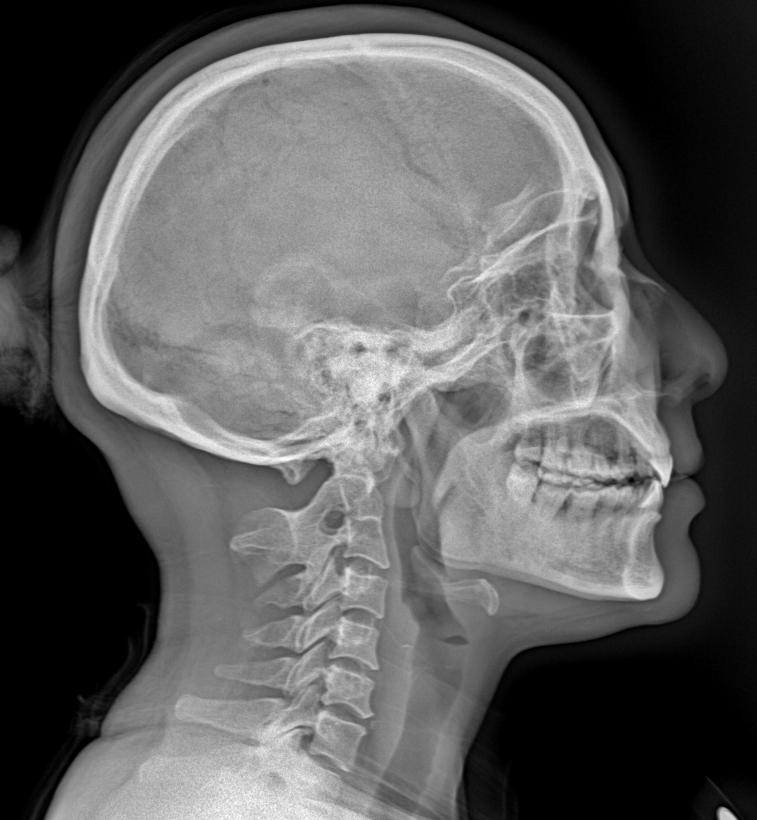

来张颈椎四位片瞅瞅大家怎么拍的